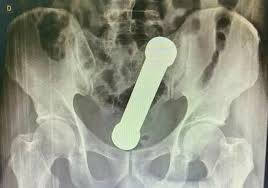

مع مرور الوقت، لم يكن الرجل قادراً على الاستقرار في مكانه، فقد كان يتلوى ألماً، وعرق بارد يتصبب من جبينه. وبينما كان الجميع يعتقد أن المسألة مجرد حصوة أو قرحة، ظهرت المفاجأة على شاشة الأشعة، حيث ظهر جسم غريب لا علاقة له أبداً بالمعدة أو الأمعاء. هنا بدأ الطبيب المسؤول يتمعن في الصورة باندهاش، حتى رفع رأسه وقال جملة أربكت الجميع: “المشكلة ليست في المعدة كما كنا نظن!”

لحظات الصمت التي سادت الغرفة لم تدم طويلاً، إذ سرعان ما تم تحويل الرجل لإجراء فحوص أكثر دقة. وكلما تعمق الأطباء في الكشف، كانت الدهشة تكبر. الرجل كان يعتقد أنه يعاني من مشكلة هضمية بسيطة، لكن ما وجدوه كان أبعد ما يكون عن التوقع.

لم يصدق أحد أن ما يخفيه جسد الرجل هو السبب الحقيقي وراء الألم.. والأغرب أن مكانه لم يكن في المعدة إطلاقاً، بل في منطقة أخرى تماماً!